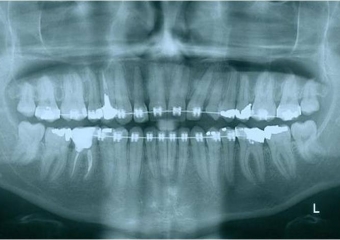

Raio X após a extração e implante imediato

Prótese provisória sobre implante